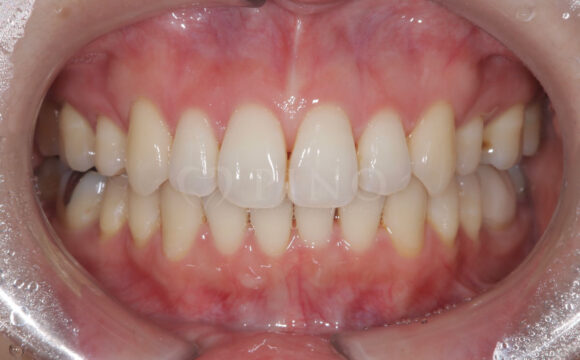

症例2:ワイヤー矯正後の後戻りが気になる(50代女性)

主訴 ワイヤー矯正後に後戻りが気になる 診断名 叢生 治療方法 マウスピース部分矯正 抜歯 なし オルソパルス なし 治療期間 10ヶ月 費用 436,000円+補綴費用360,000円 副作用・注意点 矯正後の後戻りを防ぐためリテーナーの使用が必要となる 備考 1年4ヶ月で補綴も完了した -